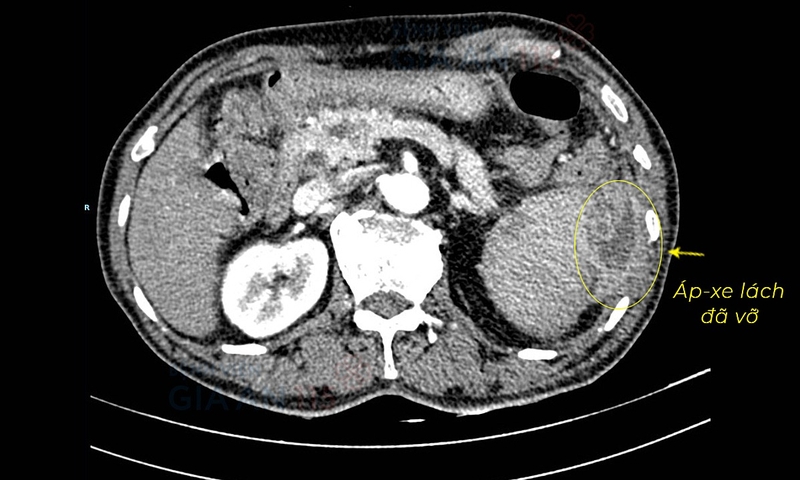

Để chẩn đoán bị vỡ lá lách, ngoài việc thăm khám các bác sĩ có thể yêu cầu bạn làm thêm một vài xét nghiệm như sau:

Bạn có thể cần ở lại bệnh viện để được theo dõi tình trạng nếu không phẫu thuật và thực hiện các can thiệp cần thiết chẳng hạn như truyền máu. Chụp CT theo dõi định kỳ được đề nghị trong trường hợp không phẫu thuật để kiểm tra xem lá lách đã lành hay chưa hoặc để xác định thực hiện phẫu thuật có cần thiết không. Phẫu thuật vỡ lá lách có nhiều thủ thuật và được phẫu thuật viên cân nhắc lựa chọn: